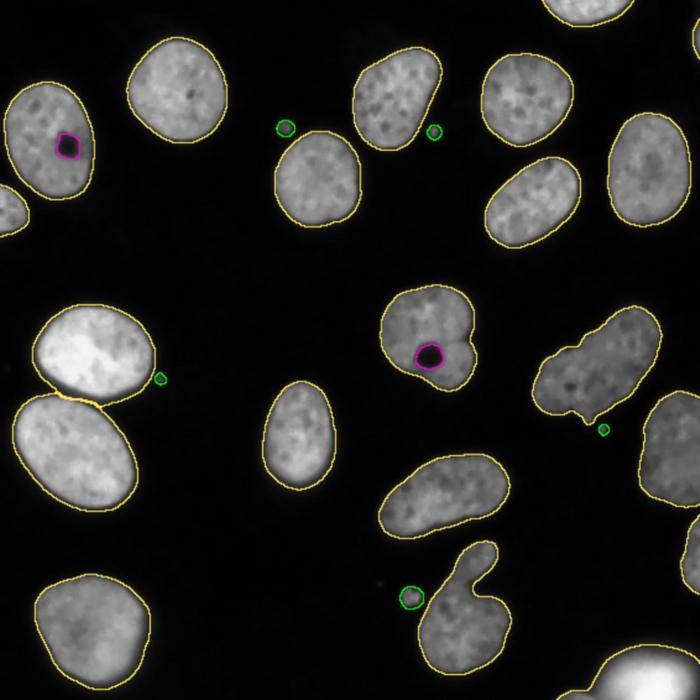

Toroidal nuclei in magenta and micronuclei in green.